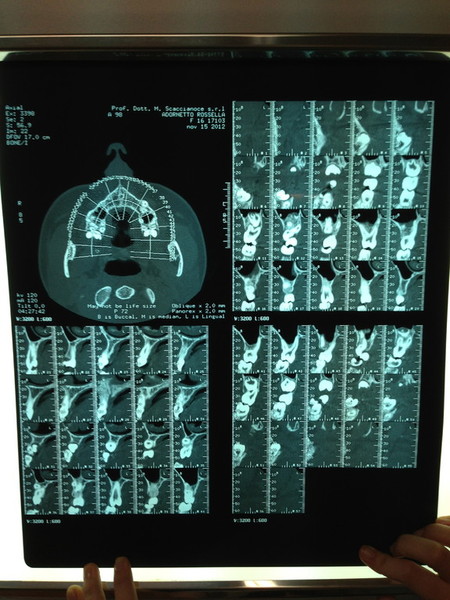

Paziente candidato a intervento di chirurgia Ortognatica